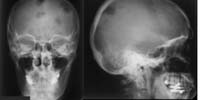

Skelettröntgen (RadioSurf) Interaktive Lernmodule zur Diagnostischen Radiologie des Skeletts für Studierende der Medizin public (öffentlich) Deutsch Studierende 1. Jahr | Studierende 2. Jahr | Studierende 3. Jahr | Studierende 4. Jahr | Studierende 5. Jahr | Studierende 6. Jahr | Ärztinnen/Ärzte in Weiterbildung Tutorial | Quiz | Mustererkennungstraining Website Anatomie

Thoraxröntgen (RadioSurf) Interaktive Lernmodule zur Diagnostischen Radiologie des Thorax für Studierende der Medizin public (öffentlich) Deutsch Studierende 1. Jahr | Studierende 2. Jahr | Studierende 3. Jahr | Studierende 4. Jahr | Studierende 5. Jahr | Studierende 6. Jahr | Ärztinnen/Ärzte in Weiterbildung Tutorial | Quiz | Mustererkennungstraining Website Anatomie